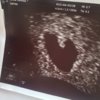

Så snudde hun skjermen

En liten knøtt som bidrar med å forme et hjerte til meg

Hjertet til knøtten banka som bare det

Jeg er lykkelig! Nå får den bare holde seg der inne en stund til